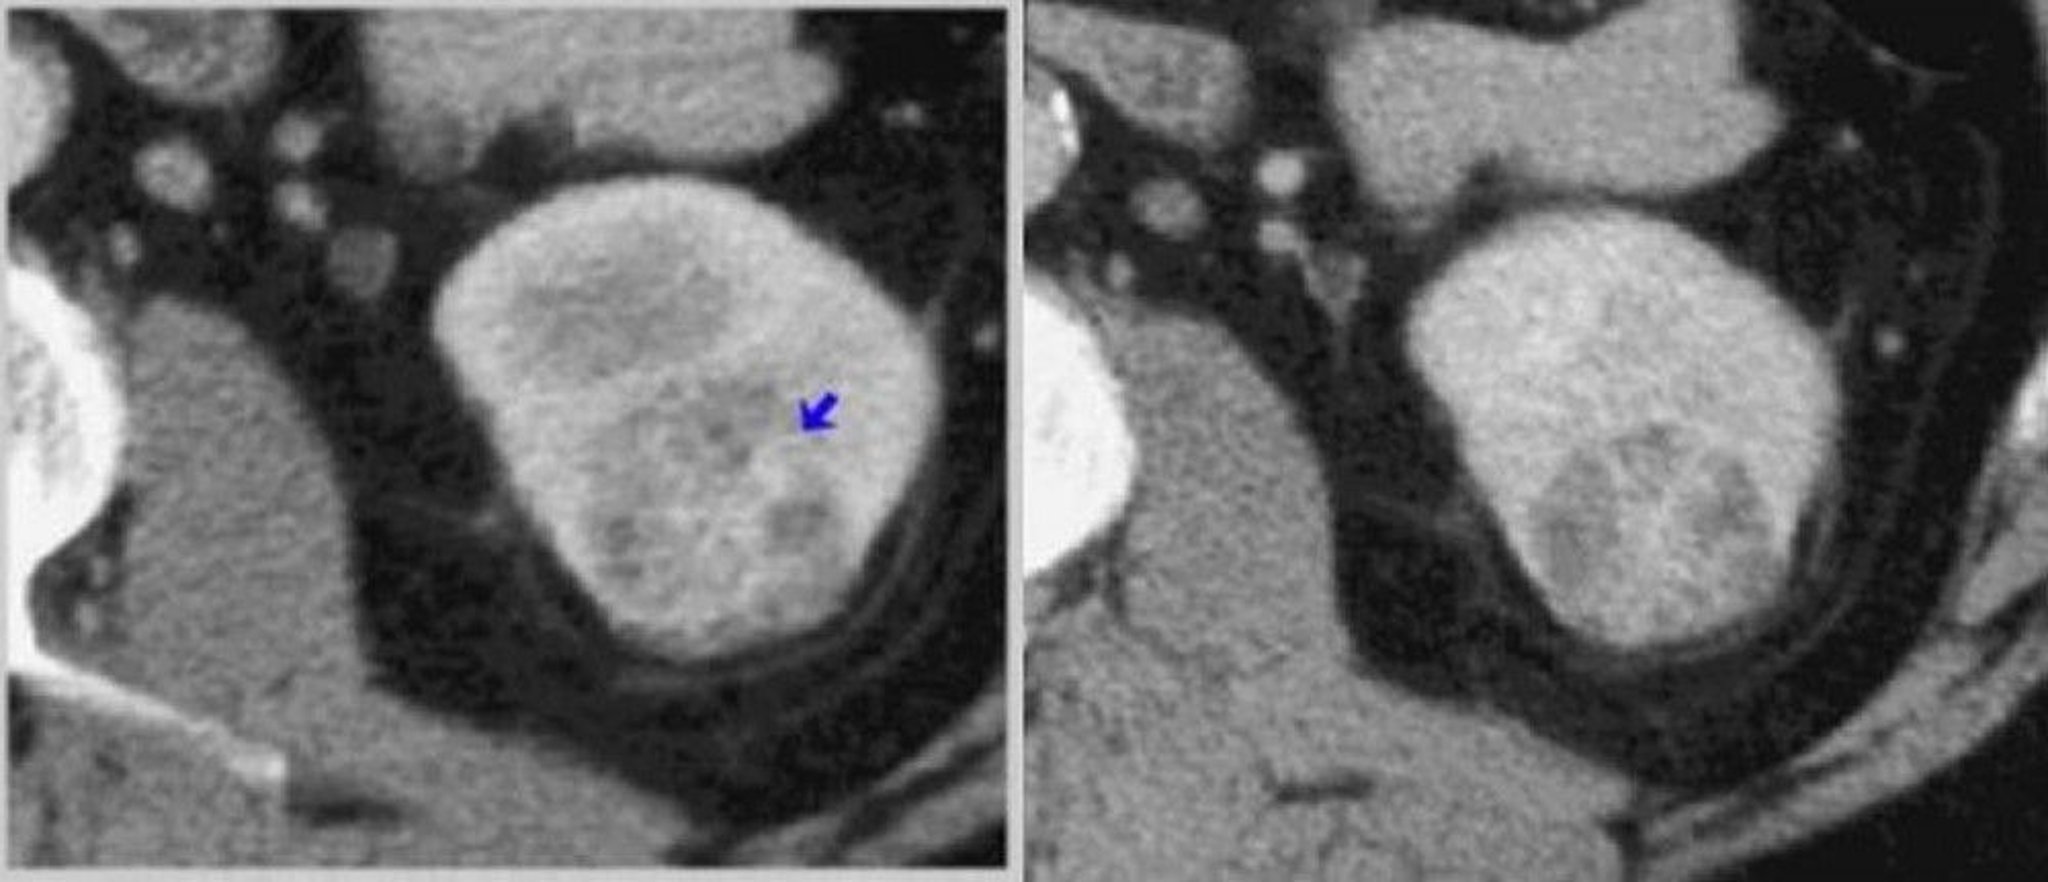

TC com contraste do rim (fases corticomedular e nefrográfica)

À esquerda, TC de fase corticomedular mostra tumor que aumenta heterogeneamente (seta). À direita, uma TC nefrográfica define melhor o tumor.